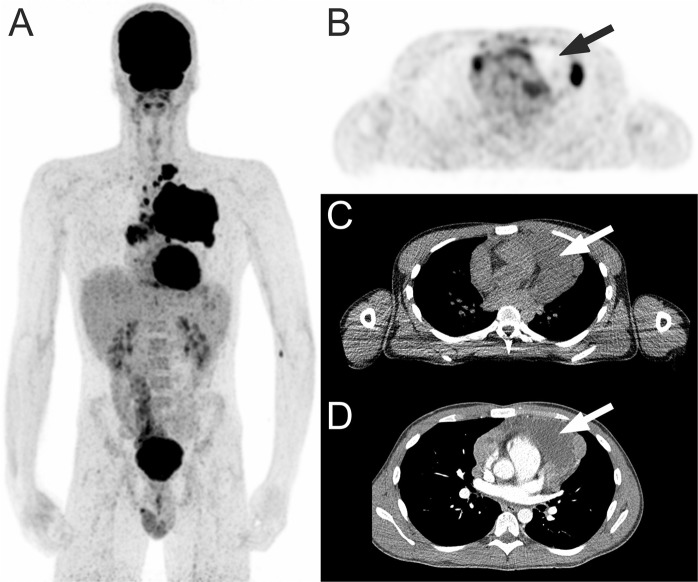

18F-FDG PET and CT review assessment of necrosisvisual was performed by an experienced reader (TCK) who was blinded to follow-up findings, including patient outcome, as previously described41,42. Briefly, all 18F-FDG PET and CT scans were visually assessed for the presence of tumor necrosis, within any nodal or extranodal 18F -FDG-avid lymphomatous lesion. Necrosisvisual was considered present if there were photopenic tumor areas on 18F-FDG PET and/or tumor areas with attenuation values between 10 and 30 Hounsfield units (HUs) on CT (Fig. 2).

Figure 2.

18F-FDG PET in a 21-year-old man with classical Hodgkin lymphoma. Coronal maximum intensity projection 18F-FDG PET shows a mediastinal tumor mass (A). Axial 18F-FDG PET with concomitant low-dose CT shows necrosisvisual with a photopenic area in the mediastinal tumor (B,C, arrows), with attenuation of around 18 HU on contrast-enhanced CT (D, arrow).